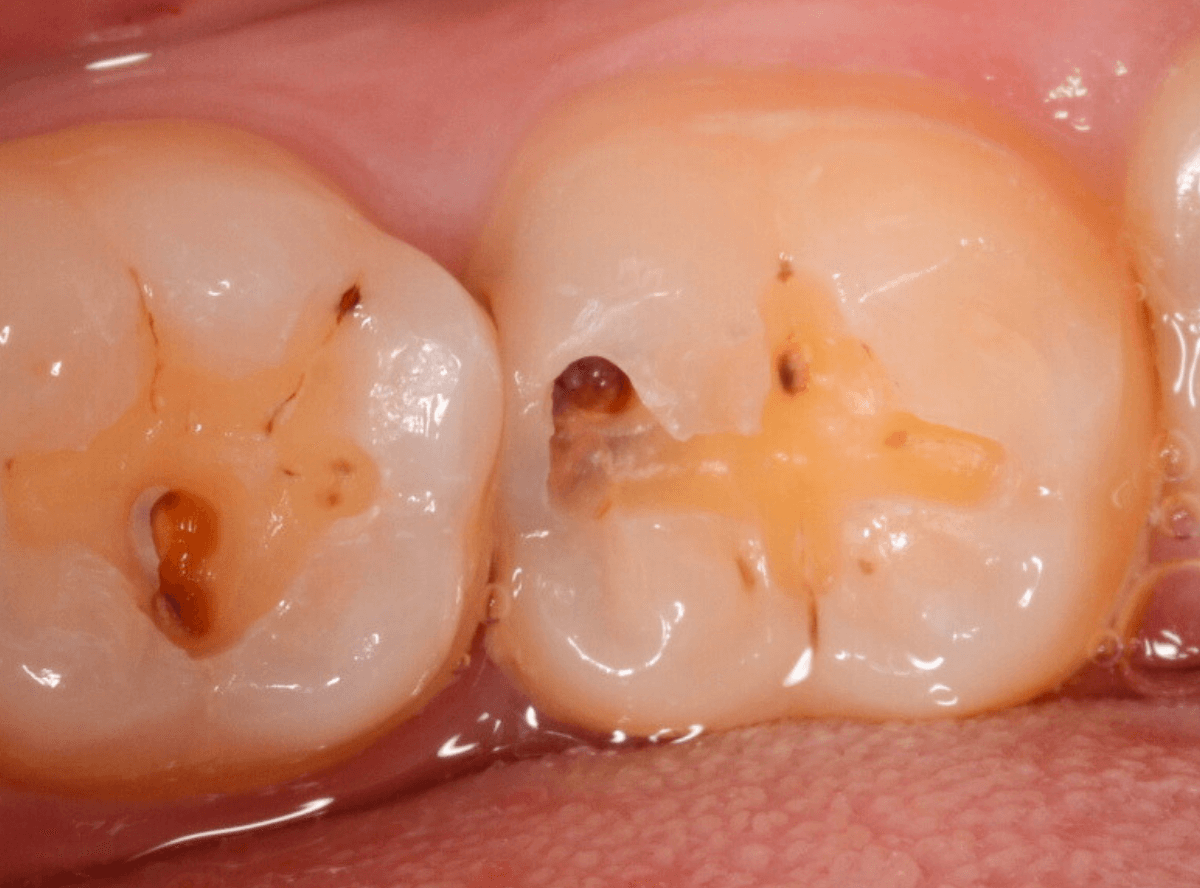

Case.8 大きな虫歯なのに、レントゲンではっきり写らない

こちらも定期検診希望で来院された患者さんです。

お口の中を拝見すると、明らかに虫歯がありました。

3本虫歯になっており、特に中央の小臼歯はかなり大きな虫歯になっているのが予想されます。

治療前にレントゲン写真で虫歯の大きさを確認するつもりが・・・あまりはっきり写ってきません。

患者さんに状況を説明して、歯を少しずつ削りながら虫歯を確認する事になりました。

まず、一番大きな虫歯と思われる部分を小さく削って確認します。

予想通り、虫歯が見えてきました。

隣りの奥歯と一緒に虫歯の治療を進めます。

色が染まっているところがまだ虫歯が残っている部分です。

2本とも、虫歯を全て取り切りました。

特に手前の歯はかなり広めの虫歯になっていました。

最終的に、手前の虫歯の除去も終わったところです。

手前の歯の虫歯は中央の歯まで達していました。

このように明らかに大きな虫歯があると診断されるような状況でも、レントゲン写真でうまく診断できない場合もあります。